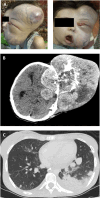

Background: Ewing sarcoma is a rare malignant neoplasm that is primarily localized in bone tissues. The prognosis for patients with a newly diagnosed localized Ewing sarcoma has been greatly improved by multimodality treatment. However, treating patients with disseminated or recurrent disease is challenging, with a 5-year overall survival rate of <30%. Case Report: A 17-year-old female with an asymptomatic tumor of the left temple underwent 3 cycles of vincristine, ifosfamide, doxorubicin, and etoposide and achieved partial remission. However, the patient refused further chemotherapy and surgical intervention and was lost to follow-up. After 7 months, the patient presented again with a sizeable tumor on her left temple and worsening symptoms. Chemotherapy with alternating cycles of vincristine, doxorubicin, cyclophosphamide, ifosfamide, and etoposide according to the EURO EWING 2012 trial was initiated. After a positive response, debulking surgery was performed, followed by postsurgical radiation, and partial remission was achieved. Conclusion: Optimal treatment protocols for recurrent Ewing sarcoma are lacking. Treatments are individualized based on the patient's response to treatment and the decisions of tumor boards. Patients with rare tumors such as Ewing sarcoma benefit from multidisciplinary collaboration, resulting in improved quality of care and treatment outcomes.